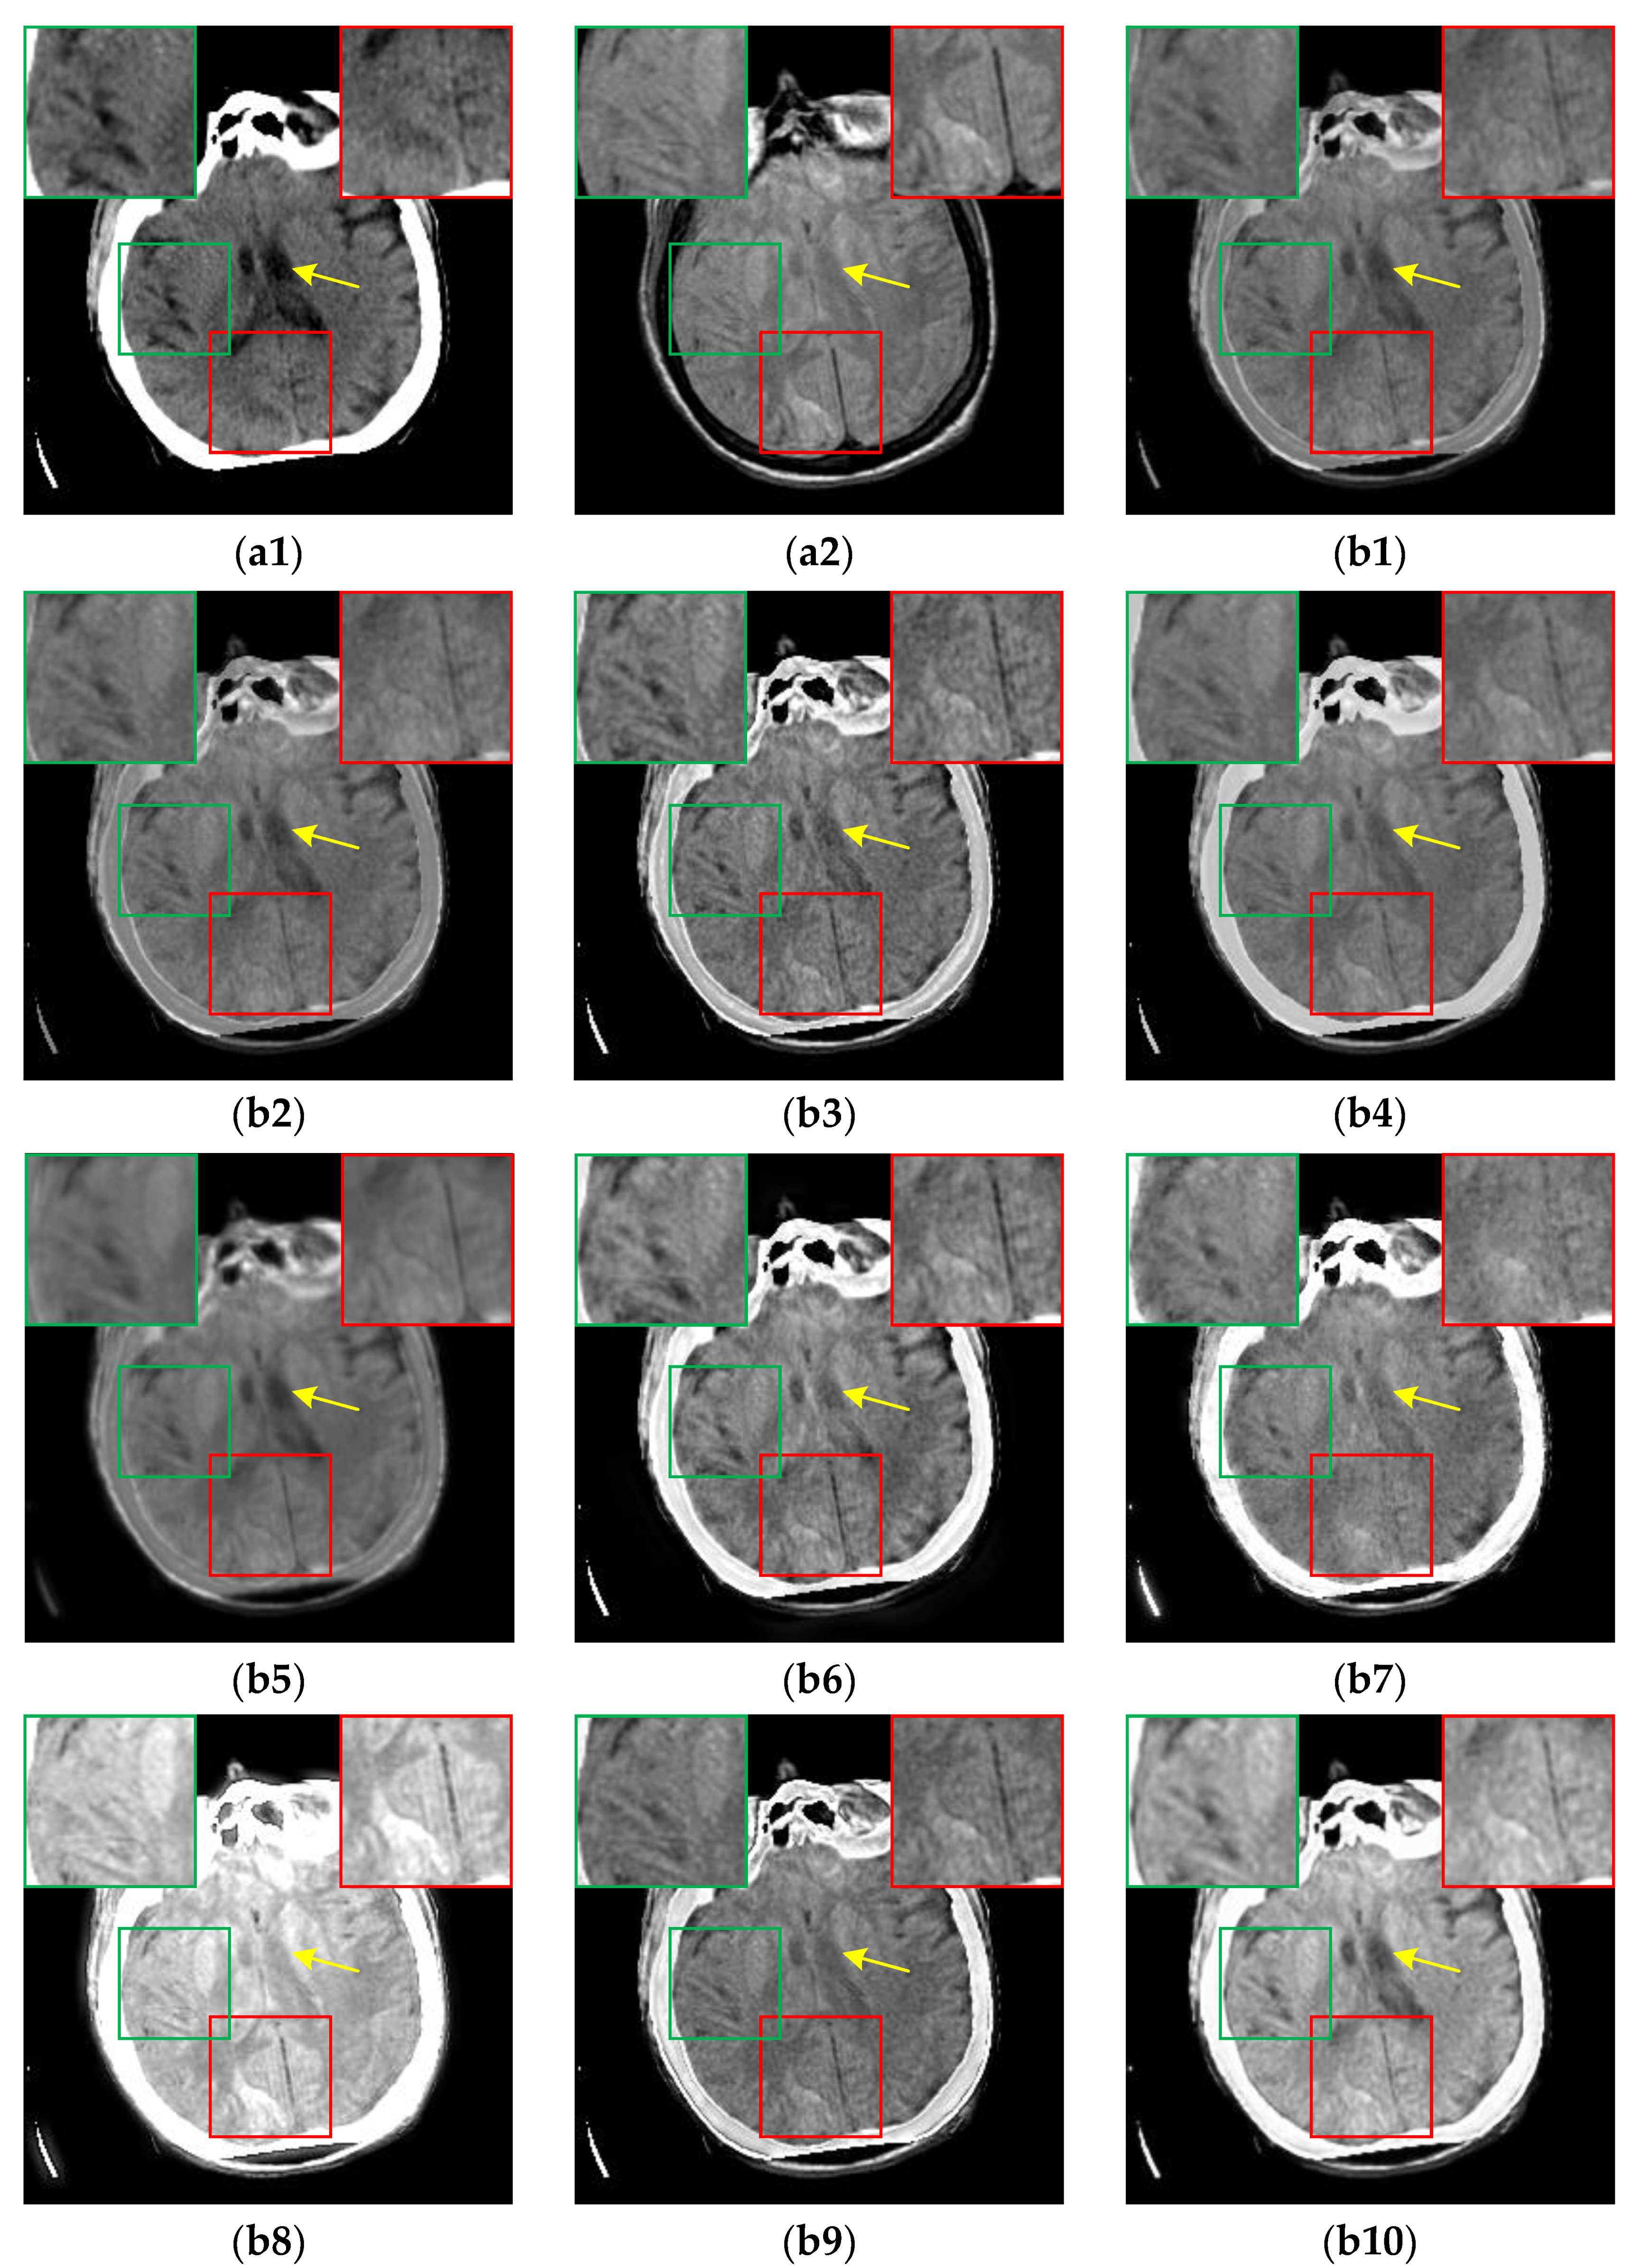

For the CT-MR image pairs from the RIRE dataset, the results are shown in Figure 9. It is evident that CIRF produces clearer image details, higher image contrast, and less loss of original information. However, U2Fusion, DenseFuse and RFN-Nest fail to effectively fuse the bright cranium from the CT image as depicted by the green arrows. As shown by the yellow arrows, IFCNN, NestFuse, PAPCNN, ReLP and CDDFuse fail to retain the low-intensity areas in the MR image, and TIF produces blocky artifacts. Besides, NestFuse and CDDFuse result in a serious loss of structural information as pointed out by the red arrows.

Figure 9. The results of all algorithms on the CT-MR image pairs from RIRE dataset. (a1) Source CT image; (a2) Source MR image; (b1) U2Fusion; (b2) DenseFuse; (b3) IFCNN; (b4) NestFuse; (b5) RFN-Nest; (b6) PAPCNN; (b7) ReLP; (b8) TIF; (b9) CDDFuse; (b10) CIRF.